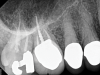

Fig 3. Case 1: Periapical imaging of the maxillary right (Fig 2) and mandibular right (Fig 3) quadrants initially showed no obvious pathology, aside from the horizontally impacted tooth No. 32. Secondary imaging following successful relief of pain after administration of an inferior alveolar nerve block revealed pre-eruptive intracoronal resorption in tooth No. 32 with resultant symptomatic irreversible pulpitis as the likely source of pain (Fig 4).

Figure 3

Although the patient's chief complaint was consistent with a degenerative pulpitis, the clinical and radiographic examination was initially unremarkable. All teeth in the maxillary and mandibular right quadrants were normally responsive to pulp sensitivity testing, and they were neither percussion nor palpation sensitive. Neither swelling nor sinus tracts were present, and the periodontal examination revealed normal probing depths and lack of mobility throughout the quadrant. Initial periapical radiographs revealed normal PDL spaces surrounding teeth Nos. 30 and 31, as well as a horizontally impacted No. 32 with a radiolucency within the crown in close proximity to the distal root surface of No. 31 (Figure 2 and Figure 3). Because the reported pain was severe, and in an effort to not only diagnose the issue but also offer some respite from the severe pain the patient was experiencing, an inferior alveolar nerve block was administered using 3.4 cc 0.5% bupivacaine with 1:200,000 epinephrine. Within 5 minutes of administration, the patient reported complete resolution of his pain.

Given the confirmation of a likely odontogenic source of pathology since pain was relieved by the block anesthesia, secondary periapical imaging was taken, which showed intracoronal resorption in the unerupted tooth No. 32 (Figure 4). Because of the visualizable pathology and signs and symptoms consistent with a symptomatic irreversible pulpitis, the patient was referred to an oral and maxillofacial surgeon for extraction of tooth No. 32. The patient reported complete resolution of symptoms following extraction of the affected tooth. Communication from the oral surgeon confirmed the diagnosis of intracoronal resorption on tooth No. 32.